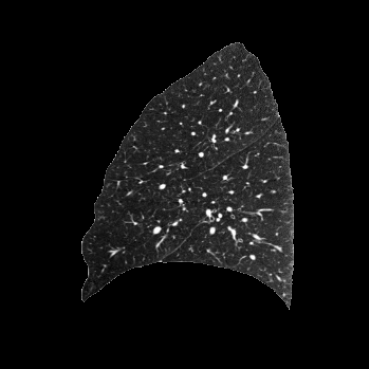

Inverse consistent rigid, affine, nonparametric, and MLP registration. We train networks on MNIST 5s using the methods in Secs. 3 and 4, demonstrating that the resulting networks are inverse-consistent. Our TwoStepConsistent (TSC) operator can be used on any combination of the networks defined in Sec. 3. For demonstrations, we join an MLP registration network to a vector field registration network, and join two affine networks to two vector field networks. Fig. 2 shows successful inverse-consistent sample registrations.

COPDGene / Dirlab lung CT. We follow the data selection and preprocessing of [23]. We train on 999 inhale/exhale pairs from COPDGene [18], masked with lung segmentations, clipped to [-1000, 0] Hounsfield units, and scaled to (0, 1). We evaluate landmark error (MTRE) on the ten inhale/exhale pairs of the Dirlab challenge dataset [4]333https://tinyurl.com/msk56ss5.

| Moving Image | Warped Image | Fixed Image | Moving Image | Warped Image | Fixed Image |